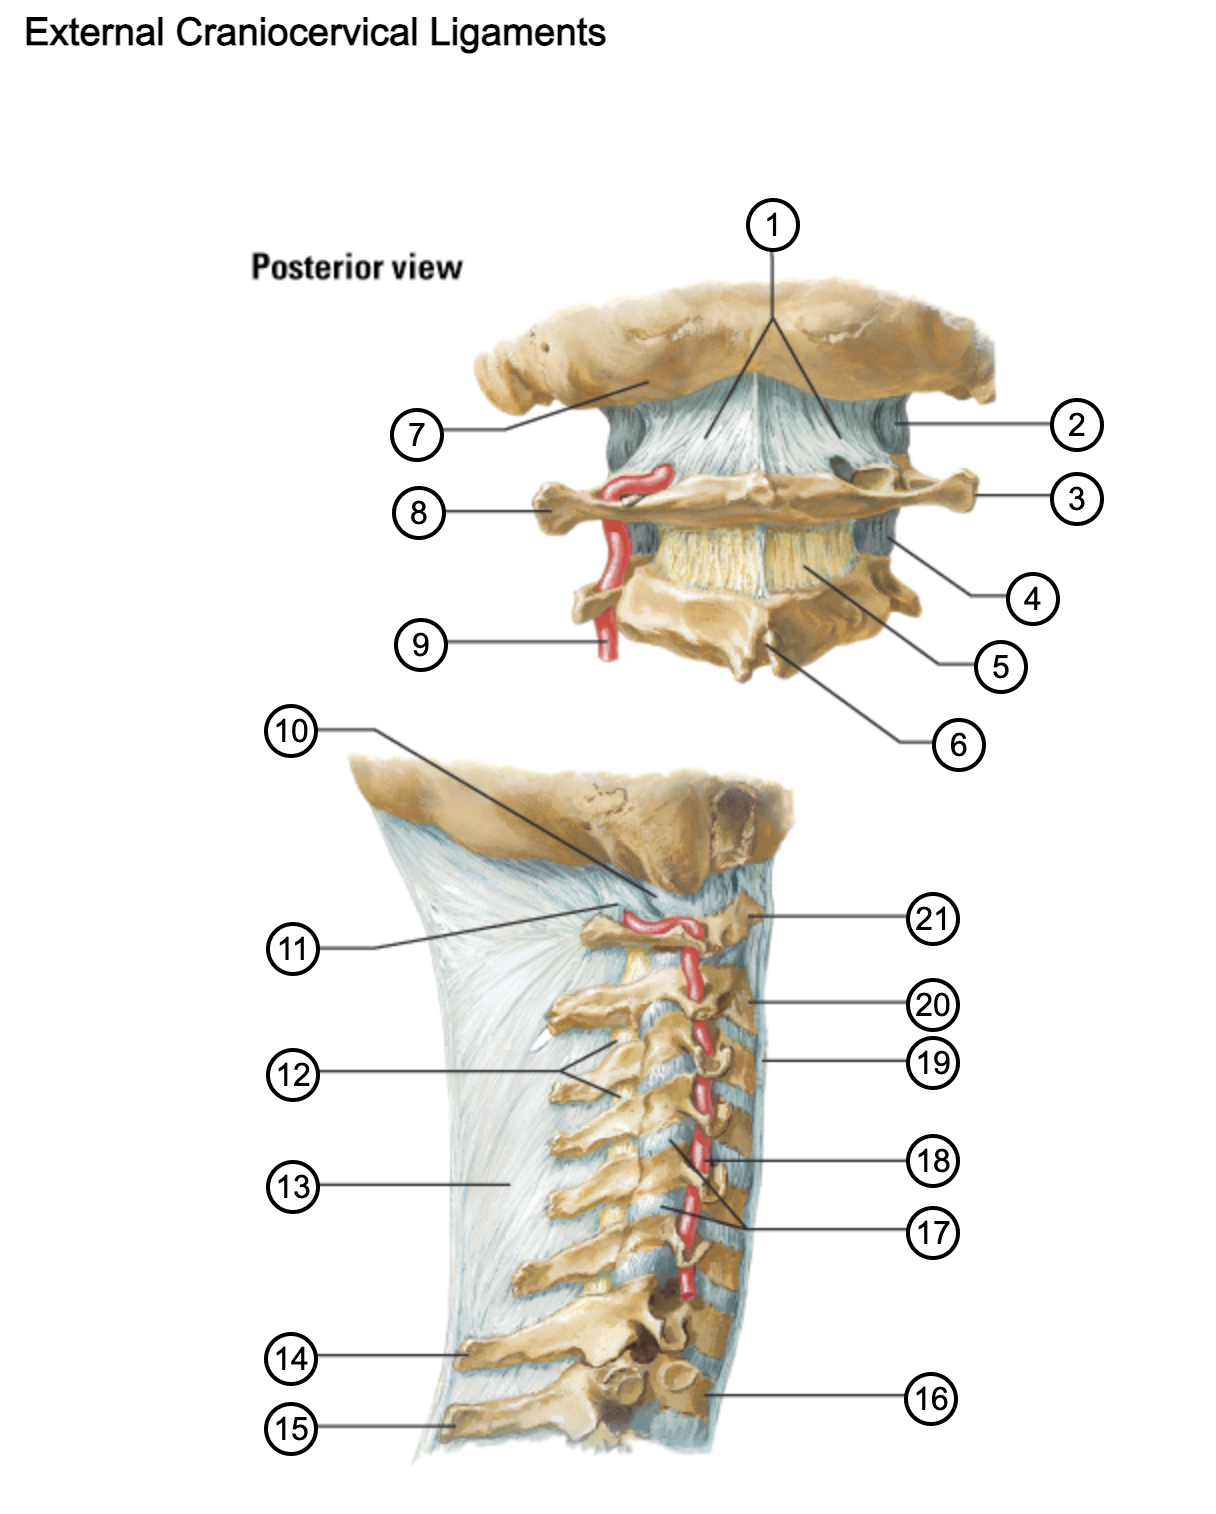

1

posterior antlantooccipital membrane

2

capsule of atlantooccipital joint

3

transverse process of atlas (C1)

4

capsule of lateral atlantoaxial joint

5

ligamenta flava

6

spinous process

7

occipital bone

8

transverse process of atlas (C1)

9

vertebral artery

10

capsule of atlantooccipital membrane

11

posterior atlantooccipital membrane

12

ligamenta flava

13

nuchal ligament

14

spinous process of C7 vertebra

15

spinous process of T1 vertebra

16

T1 vertebra

17

zygapophysical joints (C4-5 and C5-6)

18

vertebral artery

19

anterior longitudinal ligament

20

body of axis

21

Atlas (C1)